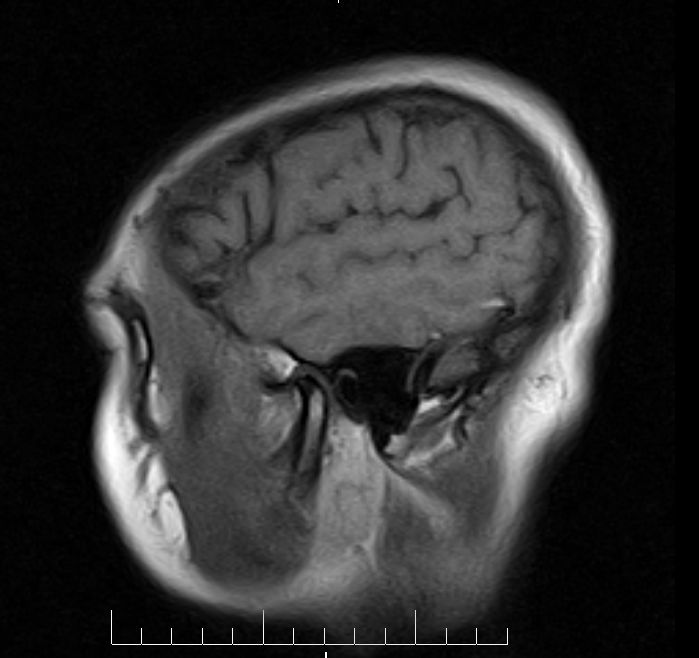

标题: MRI2379:30岁,男,癫痫10年,请各位看一下;CT示:左颞叶钙 [打印本页]

标题: MRI2379:30岁,男,癫痫10年,请各位看一下;CT示:左颞叶钙

左颞叶区见不规则点状混杂信号影

考虑血管畸形

支持2楼 左颞叶区见不规则点状混杂信号影,考虑动静脉畸形。

考虑左侧颞叶脑血管畸形(avm)。

考虑左侧颞叶脑血管畸形(avm)。----t1低等高混杂信号,t2等高信号周边较多流空血管影[冠状位明显],mra左侧大脑中动脉受压,远侧聚集.